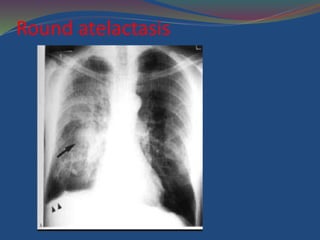

Rounded Atelectasis

 Symphysis of the visceral and parietal pleura, and

resultant infolding and entrapment of a peripheral

portion of the underlying lung

 3 to 5 cm in diameter

 Most commonly located in the paraspinal region

 Composed of a swirl of atelectatic parenchyma

adjacent to thickened pleura

Round atelactasis